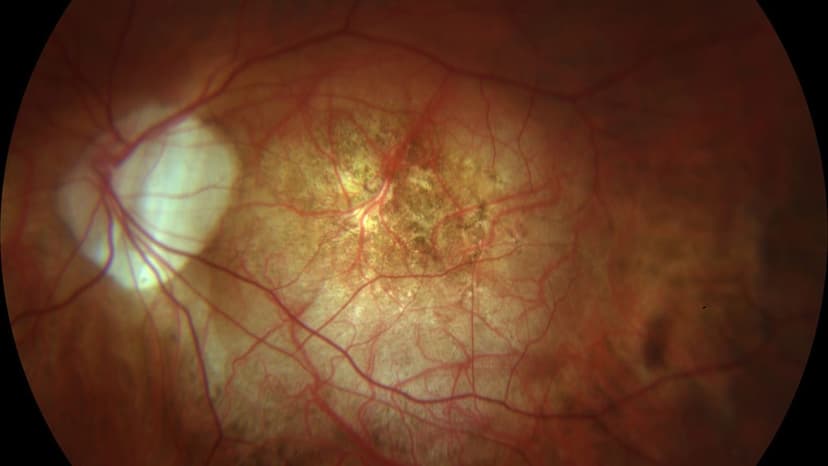

Viêm hắc võng mạc trung tâm thanh dịch là bệnh lý xảy ra khi dịch lỏng bất thường tích tụ ở phía sau võng mạc, đặc biệt tại vùng trung tâm – nơi quyết định thị lực rõ nét. Sự tích tụ này khiến võng mạc bị bong nhẹ, làm hình ảnh nhìn thấy trở nên mờ, méo hoặc biến dạng. Đây là bệnh mắt được đánh giá là tương đối lành tính, tuy nhiên nếu kéo dài hoặc tái phát nhiều lần vẫn có thể ảnh hưởng đến thị lực lâu dài.

3. Dấu hiệu nhận biết bệnh

Viêm hắc võng mạc trung tâm thanh dịch thường khởi phát âm thầm nhưng có thể gây ảnh hưởng rõ rệt đến thị lực trung tâm. Các triệu chứng giữa người bệnh có thể khác nhau, mức độ nặng nhẹ phụ thuộc vào thời gian mắc bệnh và số lần tái phát.

Những dấu hiệu thường gặp gồm:

- Nhìn mờ vùng trung tâm, thị lực giảm dần, thường ở mức khoảng 5/10–6/10; nếu bệnh tái phát nhiều lần, thị lực có thể suy giảm rõ rệt hơn.

- Hình ảnh bị méo hoặc biến dạng, đường thẳng nhìn thành cong, gợn sóng.

- Rối loạn cảm nhận màu sắc, đặc biệt là các gam màu sáng hoặc nhạt như vàng.

- Xuất hiện điểm tối hoặc bóng mờ che khuất tầm nhìn, thường nằm ở trung tâm hoặc cận trung tâm.

- Ám điểm trung tâm, có thể tự phát hiện bằng bảng ô vuông Amsler.